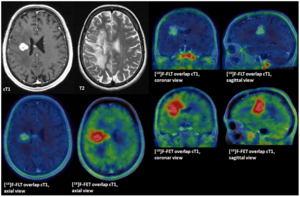

- 1.34 An Intra-Individual Comparison of MRI, [18F]-FET and [18F]-FLT PET in Patients with High-Grade Gliomas

Publication: Proc SPIE. 2014;9035:90352B. PMID: 24910722 | PDF Authors: Pallavi T, Prateek P, Lisa R, Leo W, Chaitra B, Andrew S, Mark C, Anant M. Institution: Department of Biomedical Engineering, Case Western Reserve University, Cleveland, OH, USA. Background/Purpose: Differentiating radiation necrosis (a radiation induced treatment effect) from recurrent brain tumors (rBT) is currently one of the most clinically challenging problems in care and management of brain tumor (BT) patients. Both radiation necrosis (RN), and rBT exhibit similar morphological appearance on standard MRI making non-invasive diagnosis extremely challenging for clinicians, with surgical intervention being the only course for obtaining definitive "ground truth". Recent studies have reported that the underlying biological pathways defining RN and rBT are fundamentally different. This strongly suggests that there might be phenotypic differences and hence cues on multi-parametric MRI, that can distinguish between the two pathologies. One challenge is that these differences, if they exist, might be too subtle to distinguish by the human observer. In this work, we explore the utility of computer extracted texture descriptors on multi-parametric MRI (MP-MRI) to provide alternate representations of MRI that may be capable of accentuating subtle micro-architectural differences between RN and rBT for primary and metastatic (MET) BT patients. We further explore the utility of texture descriptors in identifying the MRI protocol (from amongst T1-w, T2-w and FLAIR) that best distinguishes RN and rBT across two independent cohorts of primary and MET patients. A set of 119 texture descriptors (co-occurrence matrix homogeneity, neighboring gray-level dependence matrix, multi-scale Gaussian derivatives, Law features, and histogram of gradient orientations (HoG)) for modeling different macro and micro-scale morphologic changes within the treated lesion area for each MRI protocol were extracted. Principal component analysis based variable importance projection (PCA-VIP), a feature selection method previously developed in our group, was employed to identify the importance of every texture descriptor in distinguishing RN and rBT on MP-MRI. PCA-VIP employs regression analysis to provide an importance score to each feature based on their ability to distinguish the two classes (RN/rBT). The top performing features identified via PCA-VIP were employed within a random-forest classifier to differentiate RN from rBT across two cohorts of 20 primary and 22 MET patients. Our results revealed that, (a) HoG features at different orientations were the most important image features for both cohorts, suggesting inherent orientation differences between RN, and rBT, (b) inverse difference moment (capturing local intensity homogeneity), and Laws features (capturing local edges and gradients) were identified as important for both cohorts, and (c) Gd-C T1-w MRI was identified, across the two cohorts, as the best MRI protocol in distinguishing RN/rBT. Funding: